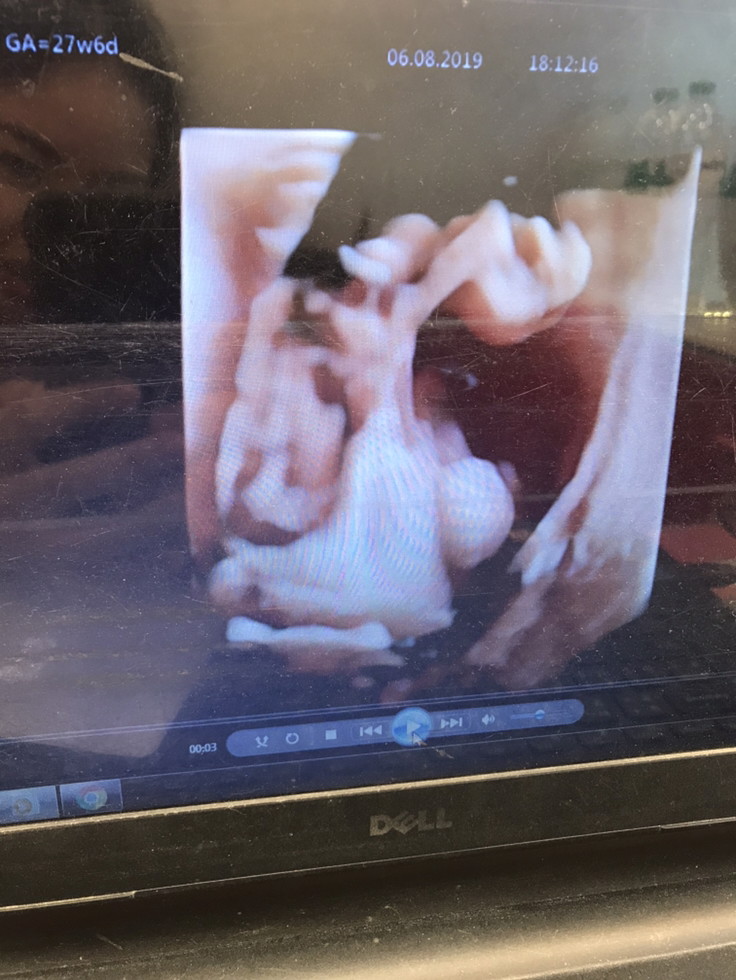

แม่ๆบ้านไหนได้ลูกชายบ้างค่ะ มาอวดรูปซาวด์กันค่ะ บ้านนี้ซาวด์มาเมื่อวานเลยค่ะ นน.889g กำหนดคลอดครั้งแรก16ธันวาไปซาวด์มาเมื่อวานหมอบอกเลื่อนวันคลอดเป็น9ธันวาค่ะ